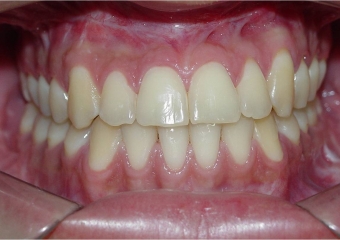

Mordida final